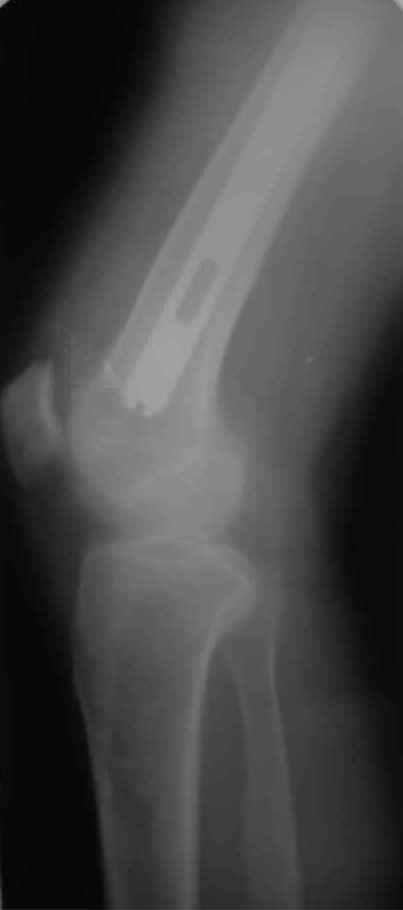

А нельзя ли увидеть и профиль бедра на всем протяжении, т.е. и весь протез, и весь стержень? И фас бы с коленом.

Спасибо!

новые снимки

Пациента удалось осмотреть недавно. Достигнутый результат сохраняется. Перелом бедра сросся. Конечность опорная и безболезненная, ходит без трости. Ножка, похоже, реинтегрировалась, как и надеялись. Снимки и фото в приложении. Комментарии приветствуются.

Надо ли что-то делать дальше, как полагаете? Убрать винты? Убрать "удлинитель ножки"? Или оставить все, как есть? Спасибо заранее.